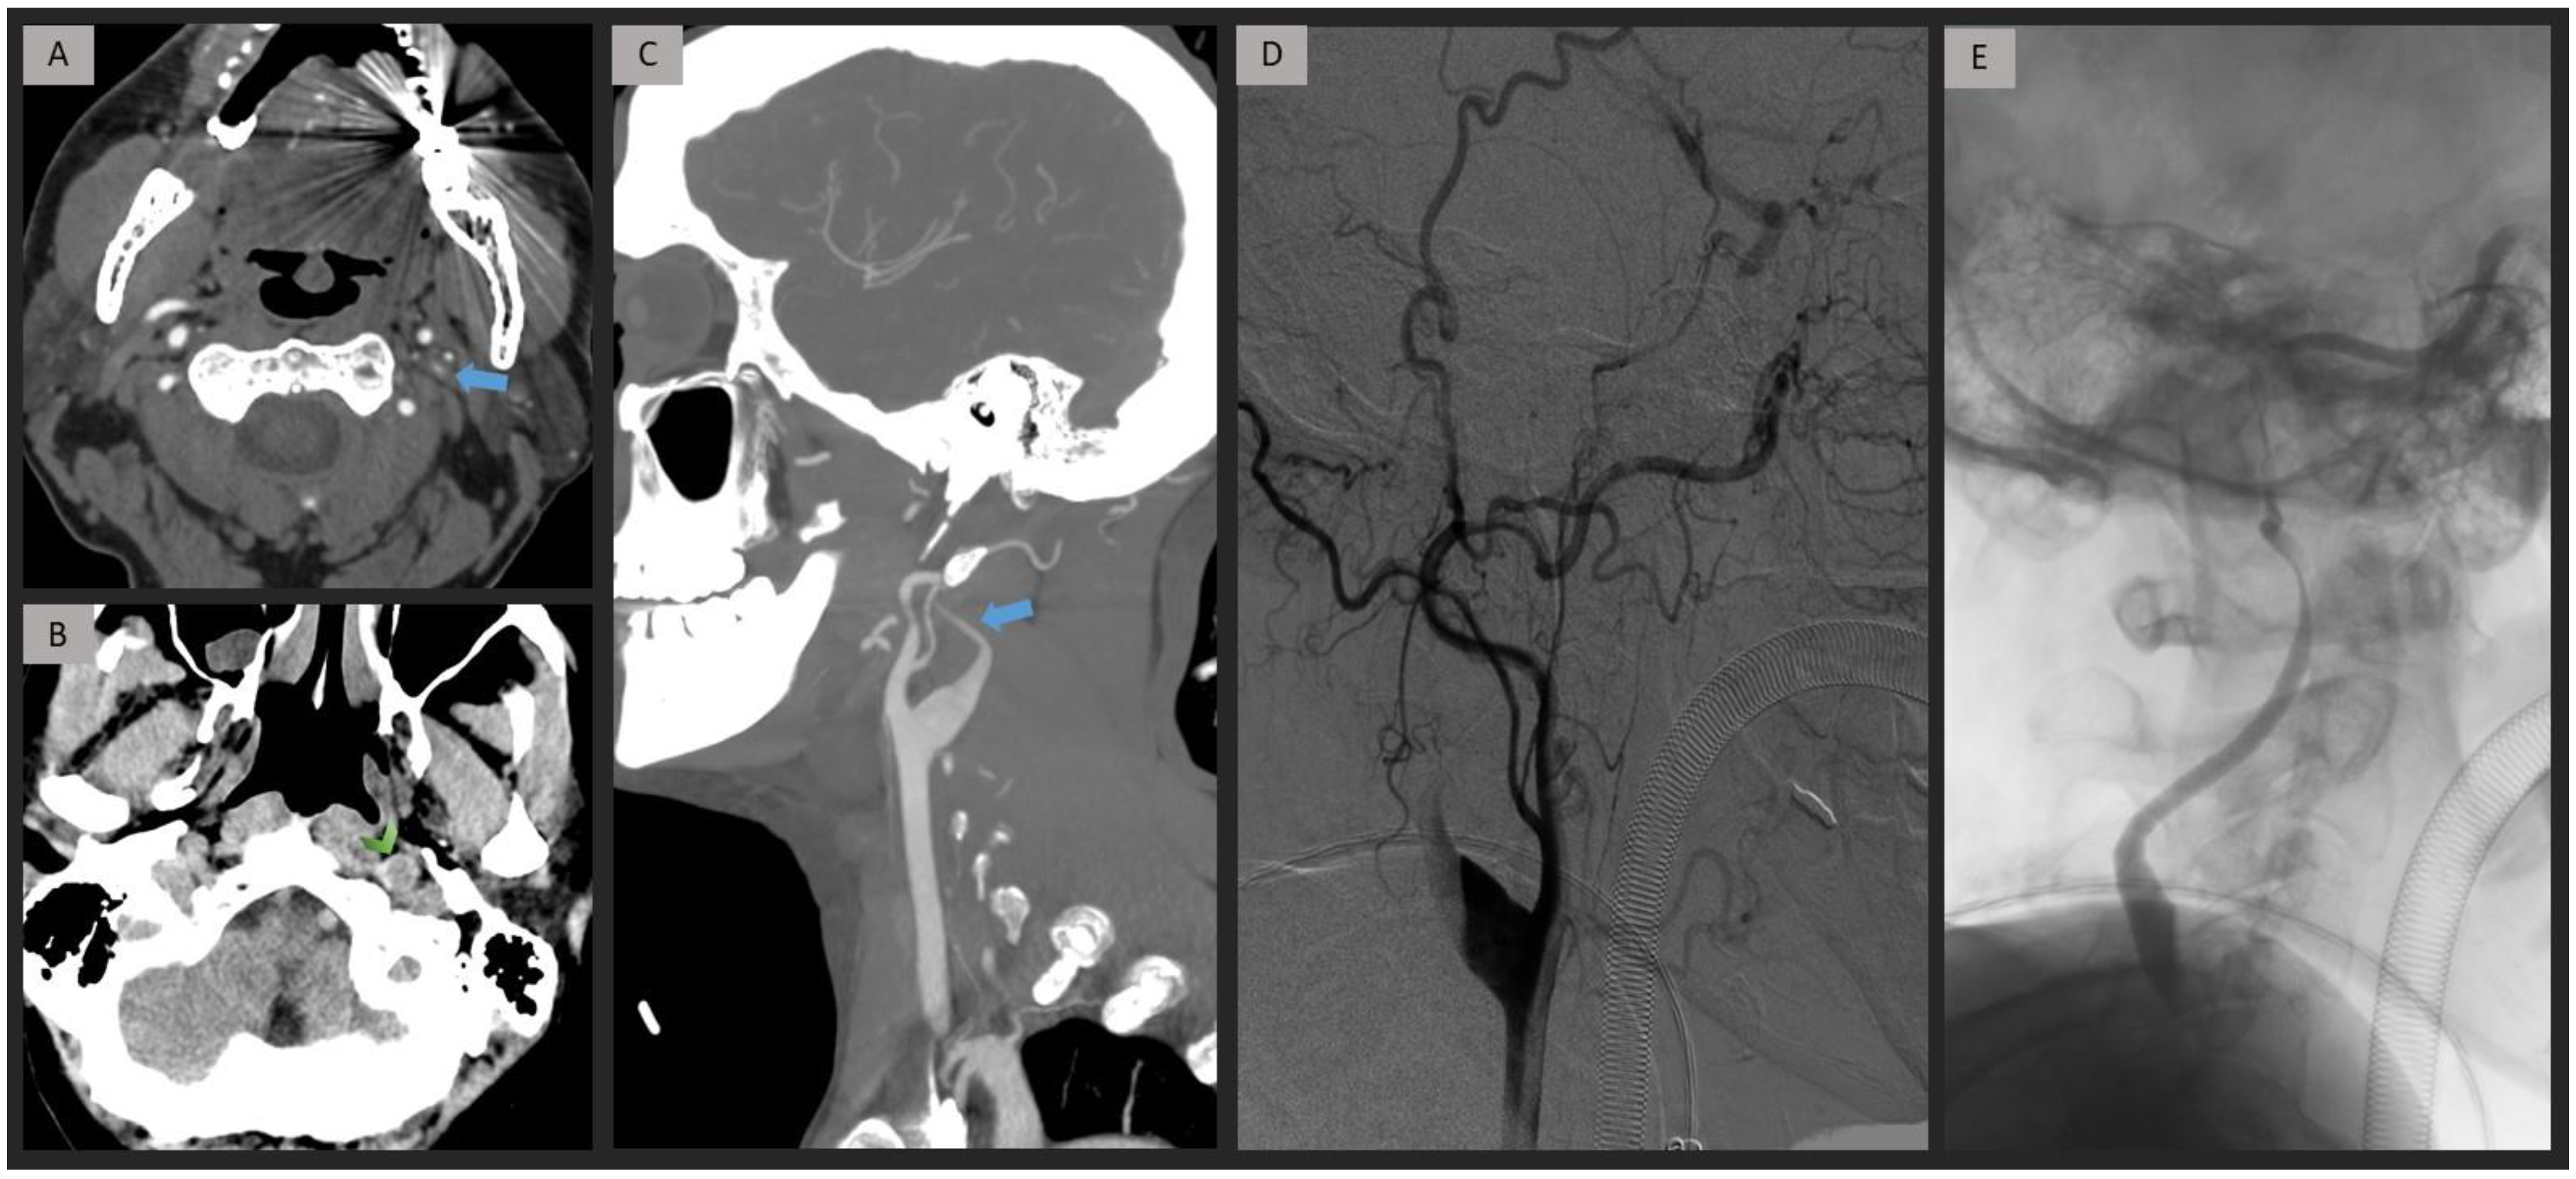

2.4. CTA Analysis

2.5. DSA Analysis

3. Results

4. Discussion